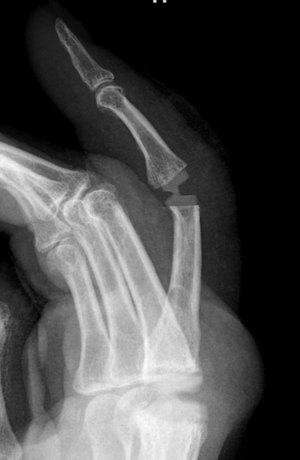

Wat is vingerartrose

Artrose of gewrichtsslijtage van de vingers is vaak erfelijk en treedt meestal op thv de eindgewrichtjes. Dit zijn de distale interfalangeale gewrichten (DIP) die pijnlijk worden, verdikken en soms scheef groeien. Er kunnen ook mucoïd cysten ontstaan.

Dergelijke artrose komt in mindere mate voor thv de proximale interfalangeale gewrichten (PIP) of metacarpofalangeale gewrichten (MCP). 1

- Radiografie